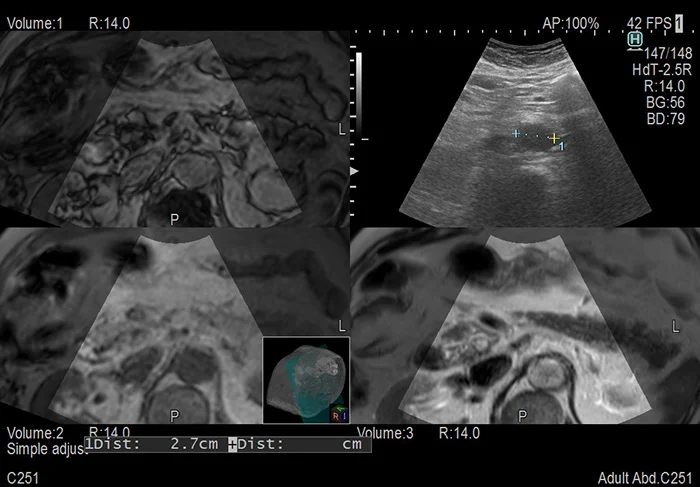

Объединённая синхронная мультимодальная визуализация

Виртуальная сонография (технология Real-time Virtual Sonography или RVS) позволяет дополнить возможности ультразвуковой системы путем синхронного совмещения ультразвукового изображения и соответствующих объемных данных компьютерной или магнитно-резонансной томографии.

Комплект специальных принадлежностей в реальном времени определяет ориентацию ультразвукового датчика и система непрерывно отображает соответствующую проекцию из объёма данных КТ, МРТ или даже УЗИ.

Сочетая в себе все преимущества различных модальностей, виртуальная сонография в значительной степени повышает эффективность диагностических исследований, так как даёт более полную и наглядную картину области интереса.

Более того, технология находит широчайшее применение при проведении инвазивных диагностических (биопсия) и терапевтических (абляция) вмешательств, предоставляя удобные средства для точного позиционирования инструментов.

Дальнейшее развитие функции - поддержка продвинутых программ: Body Motion Tracking отслеживает и компенсирует движения пациента, а также делает возможным мгновенную синхронизацию модальностей нажатием одной кнопки; Needle Tracking непрерывно отслеживает положение острия иглы и отображает предполагаемую трассу её прохождения.